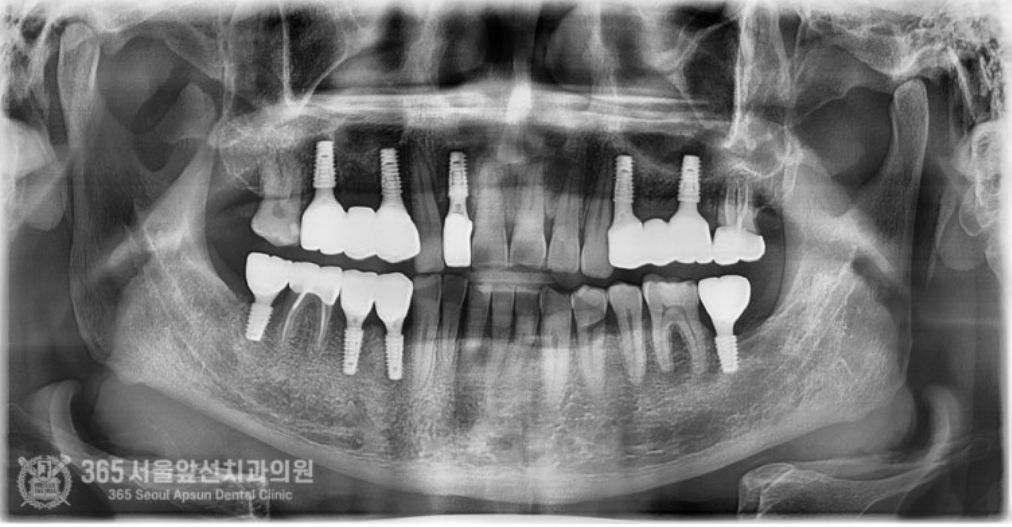

안녕하세요. 석바위시장치과 365서울앞선치과의원입니다. 오늘은 전체 임플란트 치료증례를 살펴보겠습니다. 예전에 치료해드렸던 환자분께서 소개해주신 환자분이십니다. 빵도 사다주시고 참 감사했던분이신데요 ㅎㅎ 촬영일시 : 2024.08.03. 처음 내원당시 상태는 이가 많이 없어서 제대로 밥을 먹을 수가 없어요. 잘 웃지도 못하구요. 이가 많이 없으셔서 식사도 불편하고 특히 사회생활에 불편감이 있으시다고 하셨습니다. 진단과정을 거쳐 발치할 치아는 발치하고 살려서 쓸 수 있는 치아는 살려쓰는 것으로 계획하여 치료를 진행하였구요. 촬영일시 : 2024.10.11. 임플란트가 모두 식립된 상태입니다. 치아가 없는 자리와 치아를 발치한 자리에는 임플란트를 식립하여 튼튼하게 보철물을 제작해드렸구요. 살려서 쓸 수 있는 치아는 신경치료 후 크라운으로 보강하여 마무리해드렸습니다 ㅎㅎ 치료기간은 대략 3~4개월 정도 걸렸습니다. 촬영일시 : 2025.01.12. 치료 종결 후 엑스레이 사진입니다. 임플란트가 반듯하게 잘 식립되었네요. 치아도 기존 치아색상과 조화를 이룰수있게 자연스러운 색조로 제작해드렸습니다ㅎㅎ 아주 만족하셨어요. 임플란트 치료하고 나서 인상이 확 바뀌었다는 얘기를 많이 들었어요. 이런 말씀을 해주실때마다 의사로서 뿌듯함을 느낍니다 ^^ 오늘은 소문을 듣고 내원하신 환자분을 전체 임플란트 치료를 통해 만족시켜드린 증례를 소개해봤습니다. 앞으로도 좋은 증례로 찾아뵙겠습니다. 석바위시장치과 365서울앞선치과의원이었습니다. 감사합니다. [ 치료기간: 2024년 8월3일 ~ 2025년 1월 12일 ] ※ 365서울앞선치과의원의 모든 포스팅은 각 진료과 의료진이 직접 작성합니다. 365서울앞선치과의원 블로그의 임상 케이스 게시물은 환자분께 의학적으로 정확하고 상세한 정보를 드리기 위해 각 진료과 의료진이 직접 작성하며, 모든 증례 사진은 본원 의료진이 직접 시술한 증례를 촬영한 것으로, 의료법 제23조, 제56조에 의거하며 환자분의 동의를 얻어 포스팅에 사용하였습니다. 또한 해당 케이스는 본 환자분의 치료 결과이며, 환자 상태에 따라 치료의 결과는 달라질 수 있습니다. |